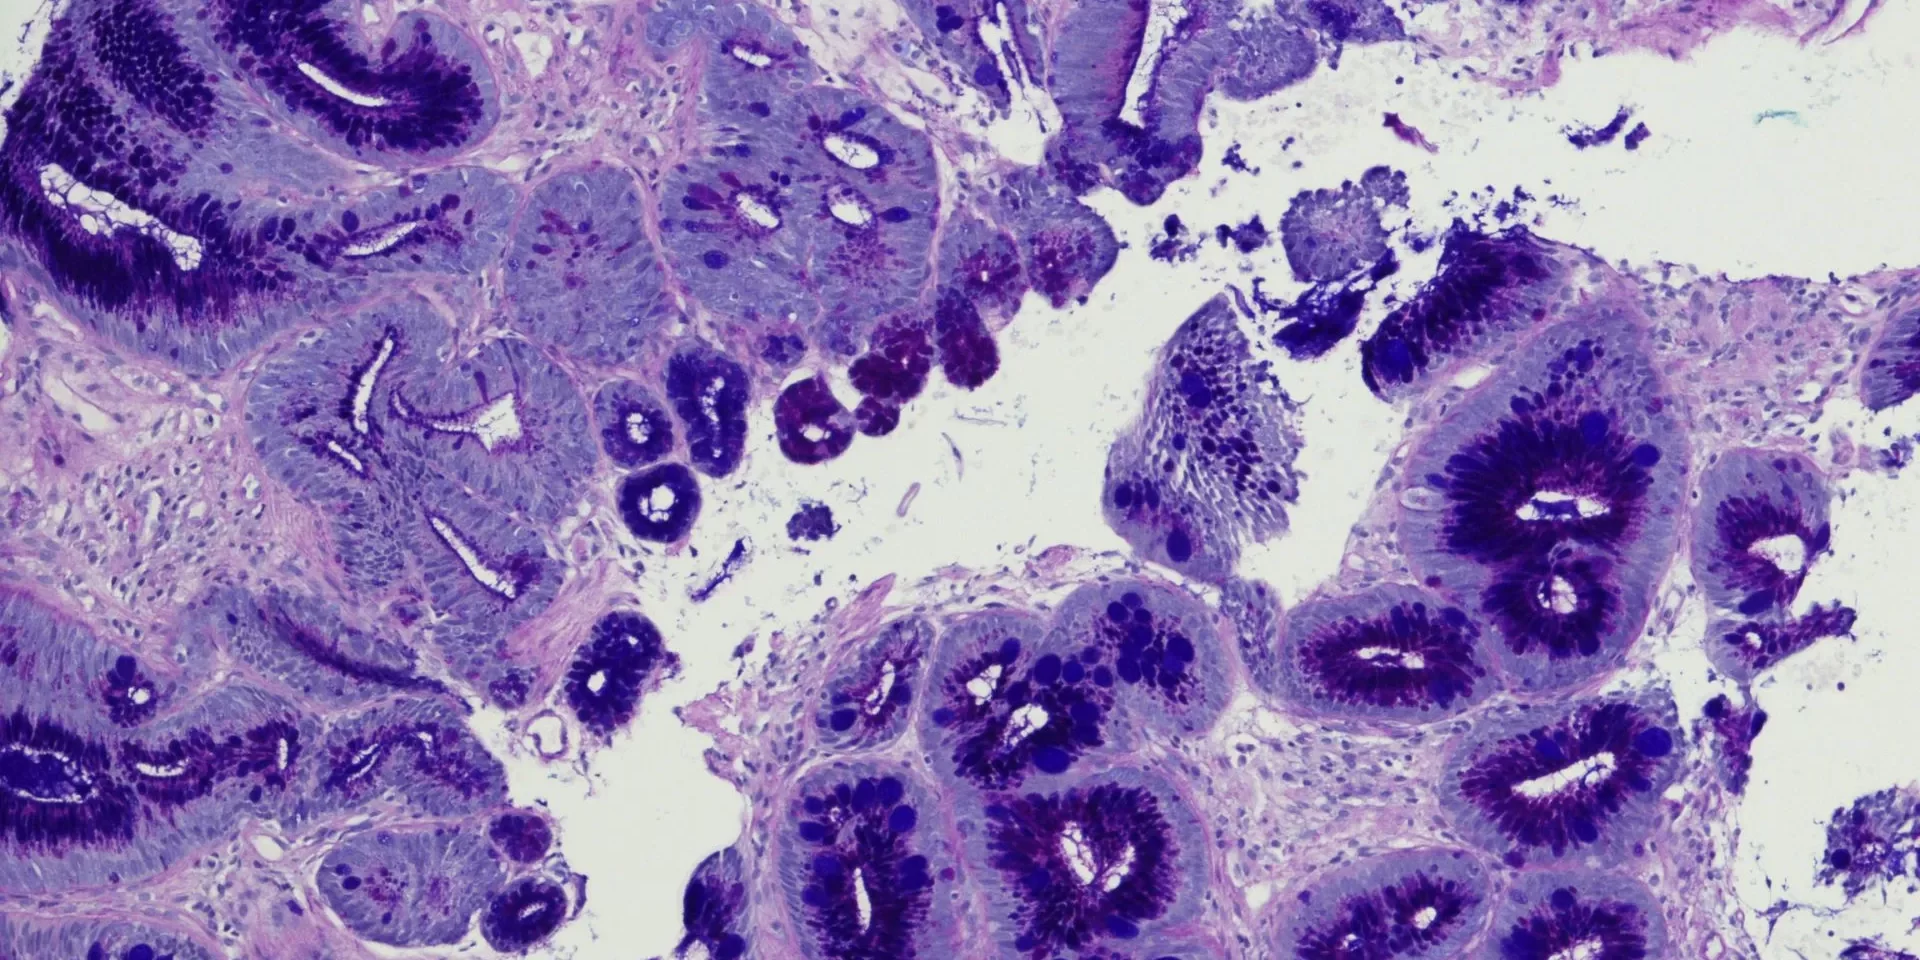

Se sottovalutato, il reflusso gastroesofageo può indurre un esofago di Barrett che è una condizione complessa precancerogena, una metaplasia, a livello della giunzione gastroesofagea in cui il normale epitelio squamoso viene modificato (epitelio colonnare) e può portare a sviluppo di adenocarcinoma esofageo. La patogenesi molecolare della malattia non è stata ancora del tutto chiarita, ma una serie di dati sperimentali ha mostrato che la somministrazione di specifici probiotici può determinare effetti positivi.

Questo studio è stato condotto con lo scopo di valutare l’effetto inibitorio dei probiotici sull’espressione di specifici marcatori in un modello in vitro. Due diverse linee di cellule esofagee di Barrett sono state selezionate per co-coltura con B. longum e Lactobacillus acidophilusallo allo scopo di misurare l’espressione genica di CDX1 (caudal type homeobox 1) e di IL-18, TNFα, p53 (soppressore tumorale) e ciclossigenasi 2.

Sono stati inoltre esaminati i risultati in termini di effetti profilattici e terapeutici. Gli effetti sono stati valutati su linee cellulari pre- neoplastiche di esofago di Barrett caratterizzate da metaplasia non displastica (CP-A) e su linee cellulari con diplasia a elevato grado (CP-D), praticamente lo stadio antecedente l’adenocarcinoma. I risultati (a 3 ore) ottenuti su linee cellulari CP-A hanno evidenziato che questi microrganismi possono interferire i biomarcatori presi in considerazione in termini quasi sempre statisticamente significativi: P53 (p=0,035 per B. longus e p=0,032 per L. acidophilus), IL-18 (p=0,014 e p<0,001), TNFα (p<0,0001 e p=0,107), CDX1 (p<0,0001 per ambedue) e COX2 (p<0,05 e p<0,0001). In co-colture con cellule CP-D i risultati sono stati ancora quasi sempre significativi: P53 (p=0,037 per B. longus e p=0,063 per L. acidophilus), IL- 18 (p<0,01 per ambedue), TNFα (p<0,01 e p<0,0001), CDX1 (p<0,0001 per ambedue) e COX2 (p<0,001 e p<0,01).

La maggiore efficacia è stata riscontrata nei test terapeutici rispetto a quelli profilattici. Secondo gli autori i risultati ottenuti indicano che il trattamento con probiotici ha delle potenzialità nella prevenzione dell’esofago di Barret e nella sua degenerazione in adenocarcinoma.